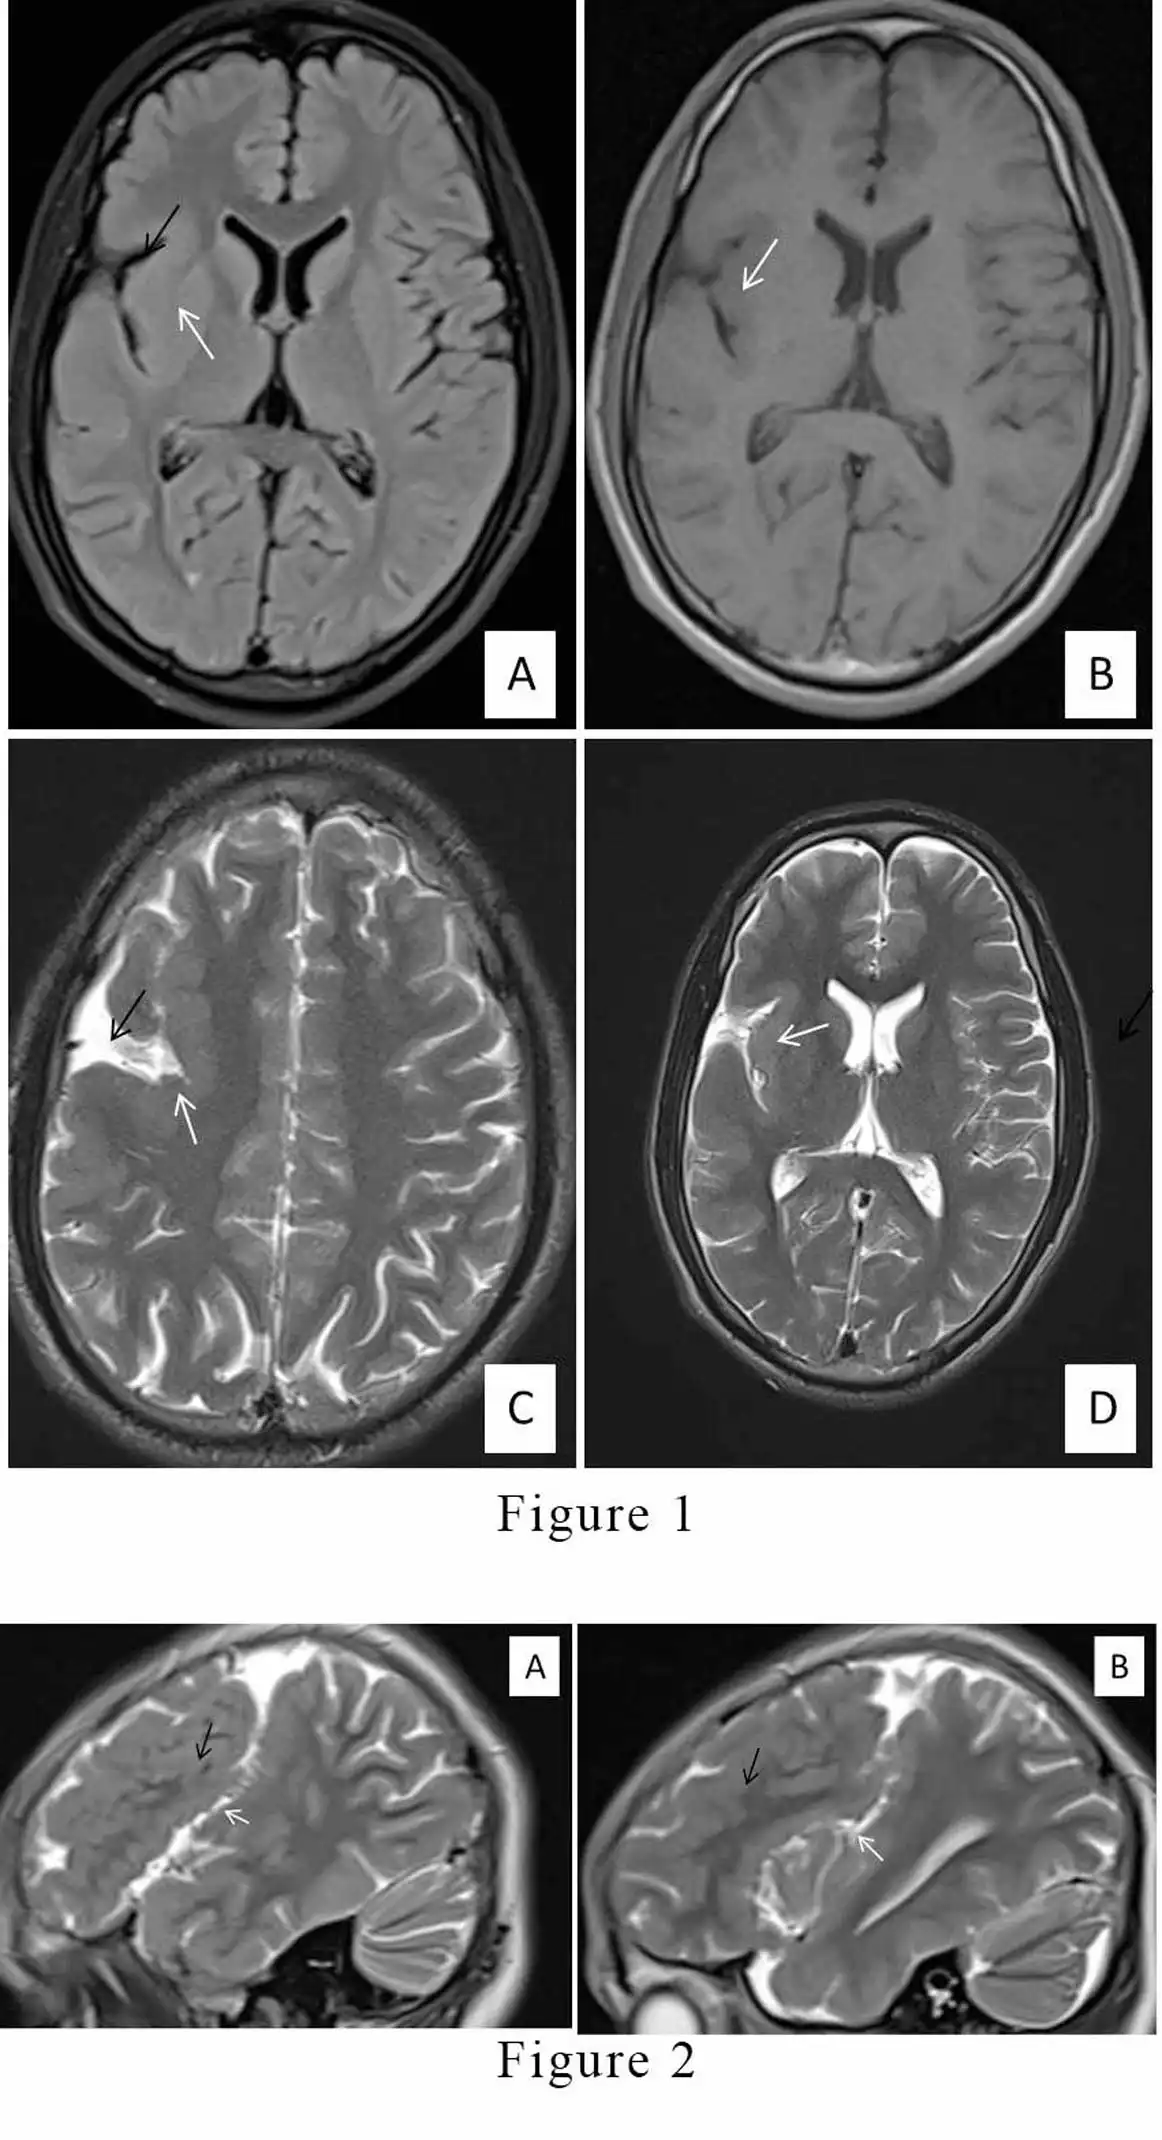

• Figure 1: Magnetic resonance images (MRI) A) Flair sequence, B) T1 sequence C), D) T2 sequence axial plane images depicting widened right Sylvian fissures (Black arrows) and thickening of right perisylvian cortex (of the right frontal and temporal lobes) (White arrows) with polymicrogyria.

• Figure 2: Magnetic resonance images (MRI) T2 sequence sagittal plane images shows widened right Sylvian fissures (White arrows) and right perisylvian thickened cortex ( Black arrows).